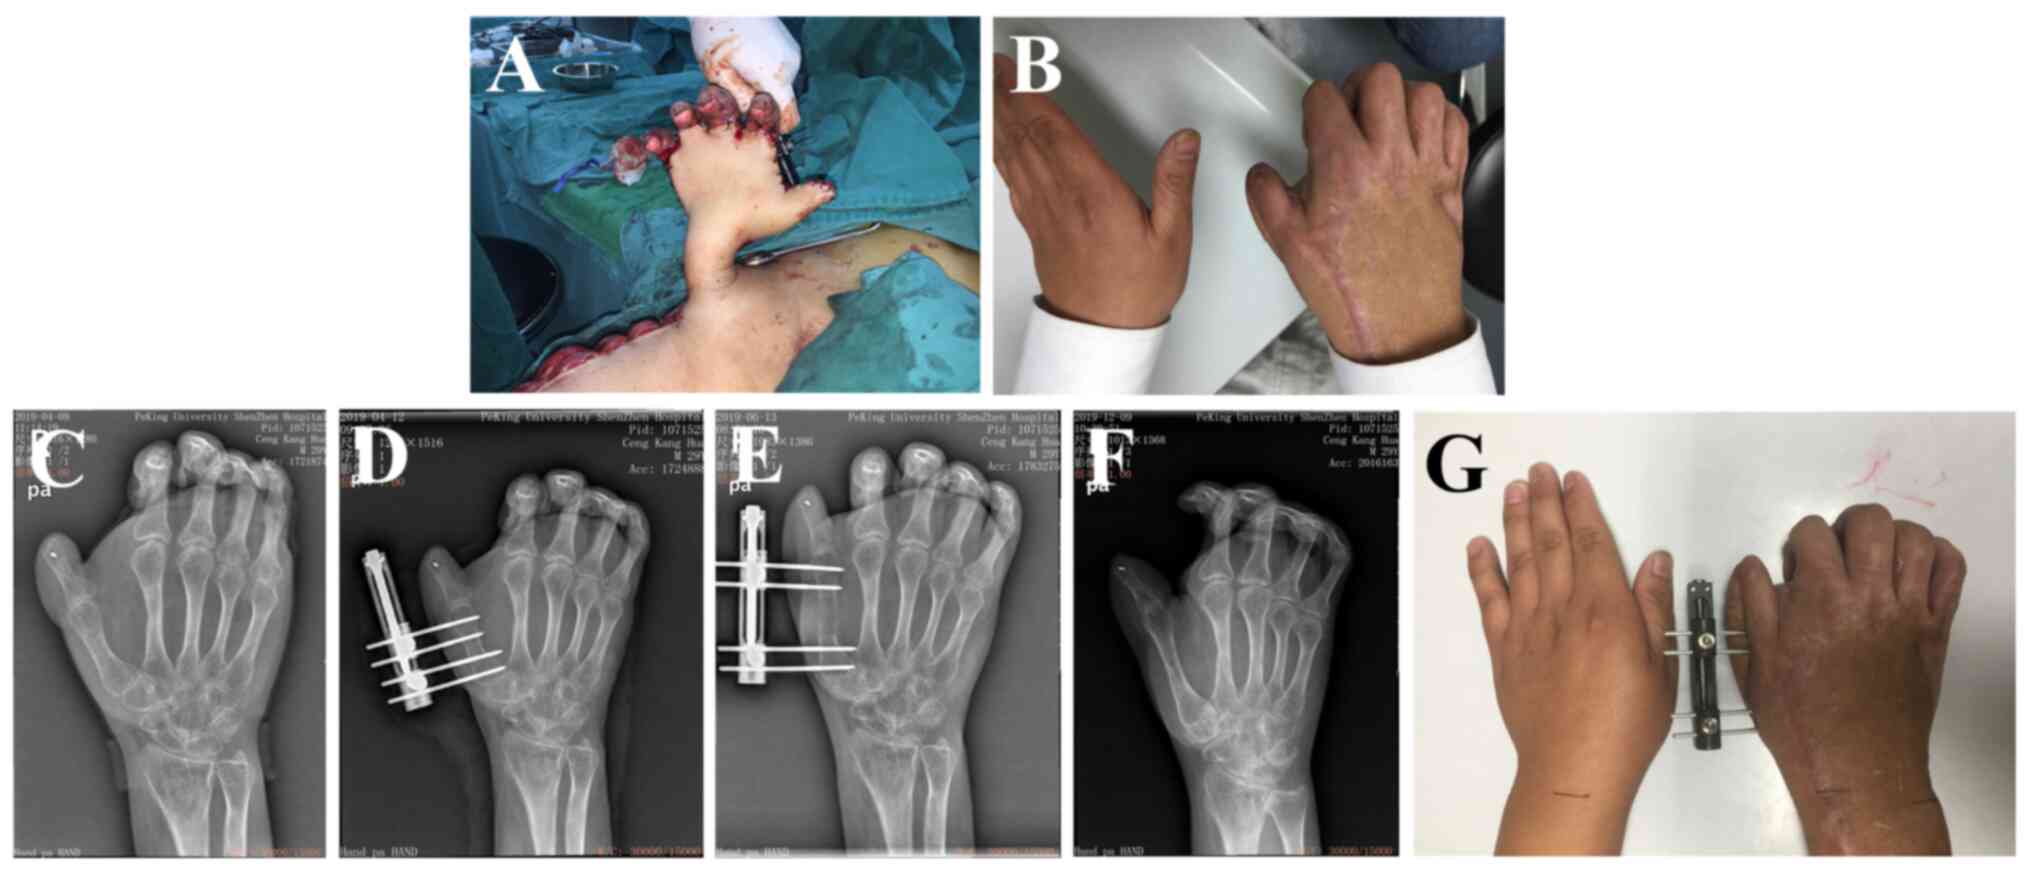

Role of microsurgical techniques combined with Ilizarov techniques in limb salvage and functional reconstruction of thermal‑crush injuries of the hand: A case report

The Ilizarov technology was proposed by Former Soviet orthopedic physician Ilizarov. It is a medical method to reconstruct missing tissues. Ilizarov technology combined with soft tissue stretching technology is of great significance in the treatment of common orthopedic problems like bone defects, finger absence, joint contracture and joint stiffness following thermal‑crush injuries of the hand. In the present study a 25‑year‑old male patient sought for limb salvage treatment 1 month after sustaining thermal‑crush injuries of the right hand and forearm. The patient had been treated by another hospital with multiple procedures of debridement, and recommended for forearm amputation. The patient was diagnosed with: i) Postoperative infection of thermal‑crush injuries of the right hand and right forearm; ii) comminuted open fractures of the proximal and distal phalanges of the right thumb; iii) osteomyelitis; iv) palm skin defects with exposed tendons; and v) skin defects of the opisthenar and the forearm. After a series of treatments including debridement, removal of necrotic tissue, tissue transplantation, skin pedicle, bone lengthening, external shaping, tissue release, joint fusion, traction and rehabilitation exercises, the patient recovered some hand function. Overall, thermal‑crush injuries of the hand are severe, complicated combined injuries composed of both heat burn and compression injury and their treatment is challenging. Overall, microsurgery combined with Ilizarov technology can effectively reconstruct the function of complex thermal‑crush injuries of the hand.